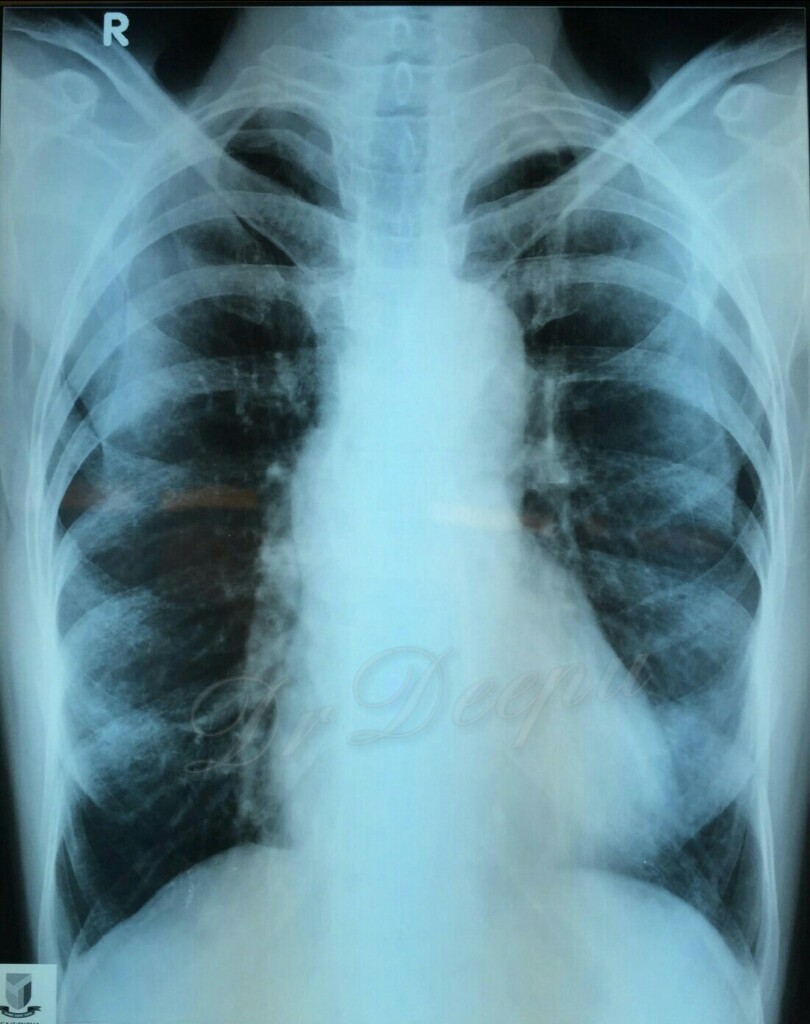

Chest Xray showing an interstitial pattern suggestive of eosinophilic Chest X Ray Eosinophilic Pneumonia Eosinophilic lung diseases are a heterogeneous group of disorders that are characterized by excess infiltration of. Eosinophilic pneumonia represents a heterogeneous group of lung disorders characterized by the presence of peripheral blood eosinophilia (defined as an. Characteristic imaging findings are often detected with chest radiography, and ct best shows parenchymal abnormalities. The integration of clinical, radiologic, and. Response to therapy. Chest X Ray Eosinophilic Pneumonia.